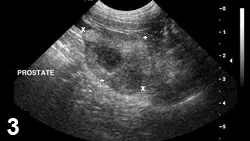

FIGURE 4

Sagittal view of a prostate in a castrated dog. Prostatic mineralization suggests neoplasia.

FIGURE 5

Prostatic adenocarcinoma. Sagittal image of an intact canine prostate showing characteristic BPH striations ventrally, but hypoechoic nodules (cursors) present within the dorsal parenchyma. Nonhomogenous prostatic parenchymal appearance should prompt evaluation with a biopsy.

• Diagnosis of PN can be supported by intraprostatic mineralization and complex parenchymal changes on ultrasonography (Figure 4).

• Multiple prostatic pathologies can be present in any patient (Figure 5).